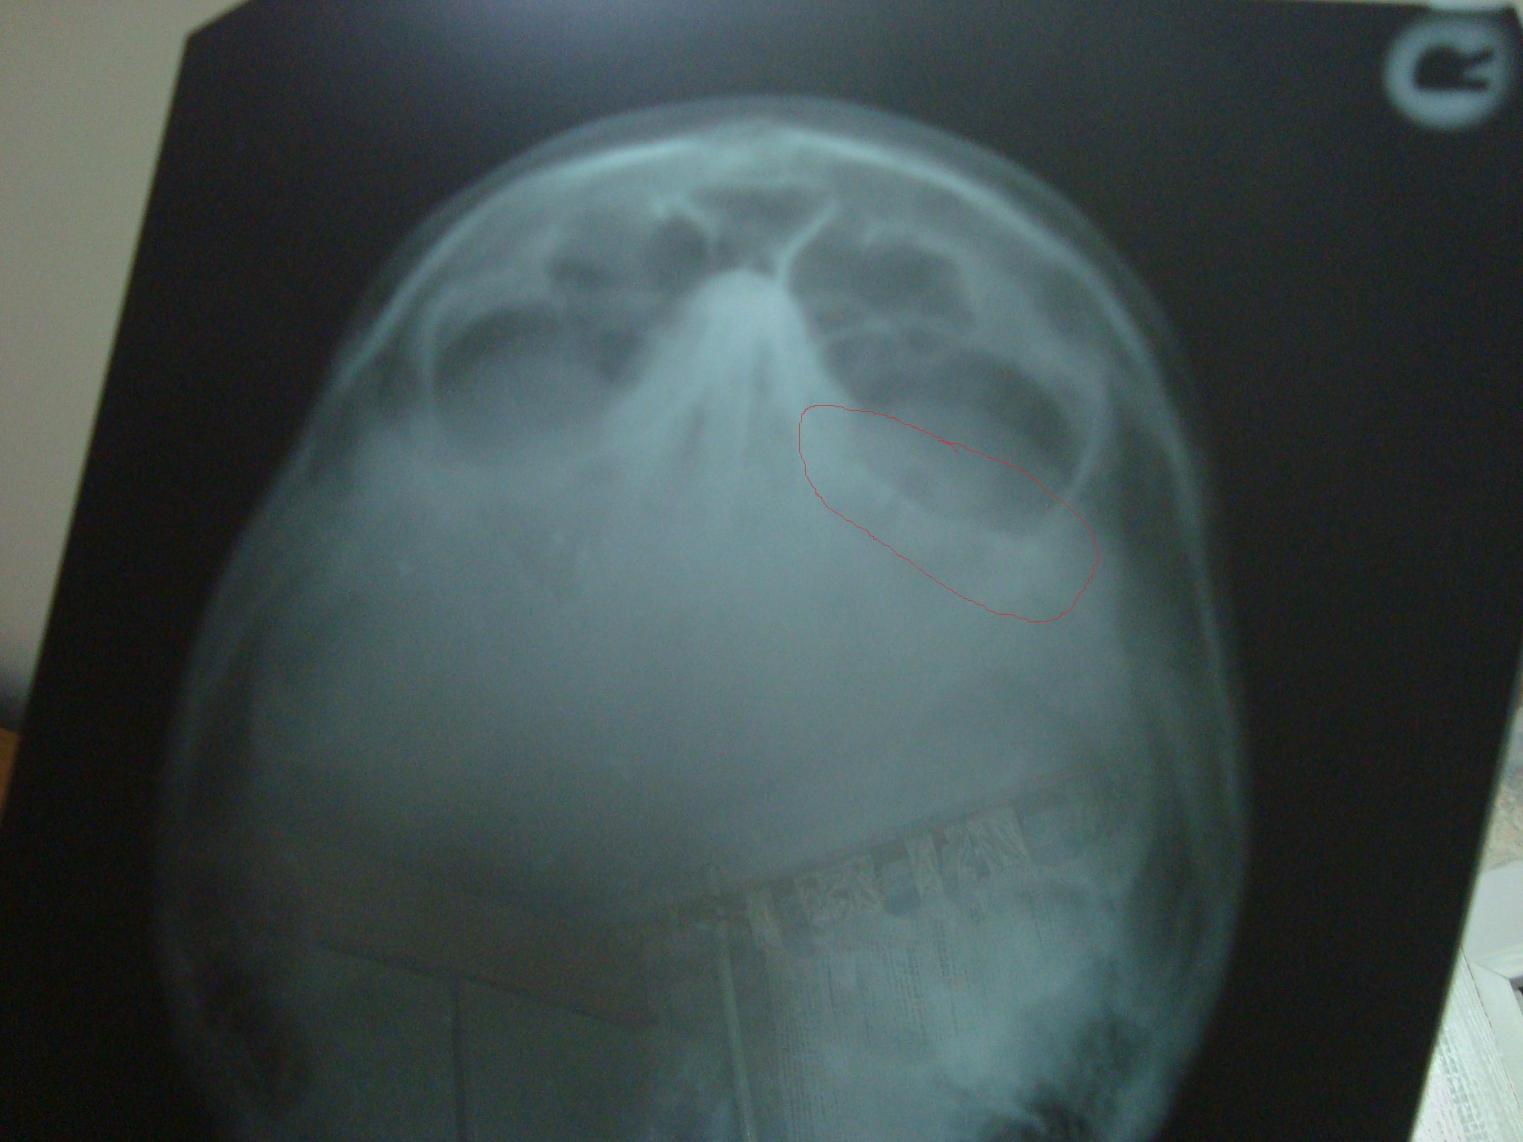

там перелом скуловой кости и медиальной стенки носа

поставили ти платину с болтами

болтами прихватили осколки кости, а пластину к черепу, под глаз эластичную сетку, чтоб глаз не "проваливался" пока заживет глазница